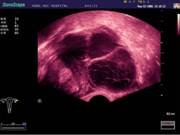

- Брюшная полость - Гинекология - Акушерство - Урология |

В Центре современных медицинских технологий «АКВА МЕД МАРИН» при помощи профессиональной аппаратуры, проводится: